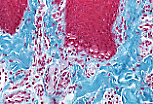

| A型角化复层扁平上皮 | ||

A型角化复层扁平上皮(掌部皮肤)的各层结构发育完善,易于识别。 | |

基底层 主要由柱状细胞构成,其基底面有微小的插入突起,有助于表皮与基膜的黏附。 | |

角质形成细胞离开基底层后开始成熟分化。

棘层 中的细胞呈多角形,嗜酸性,通过指状细胞突起相互嵌合。 |

薄切片(2微米厚)可清晰显示棘层的嵌合结构,其“齿状”部分由相邻角质形成细胞的突起构成。 这些突起处可见结节状增厚结构(比佐泽罗小体)。 | |

颗粒层 中的角质形成细胞核固缩,细胞质内充满透明角质颗粒(丝聚合蛋白原)。 | |

角质层 (A型角化上皮,掌跖区)由多层无核角质形成细胞堆叠而成, 细胞内充满角蛋白,构成防水的屏障结构。 | |